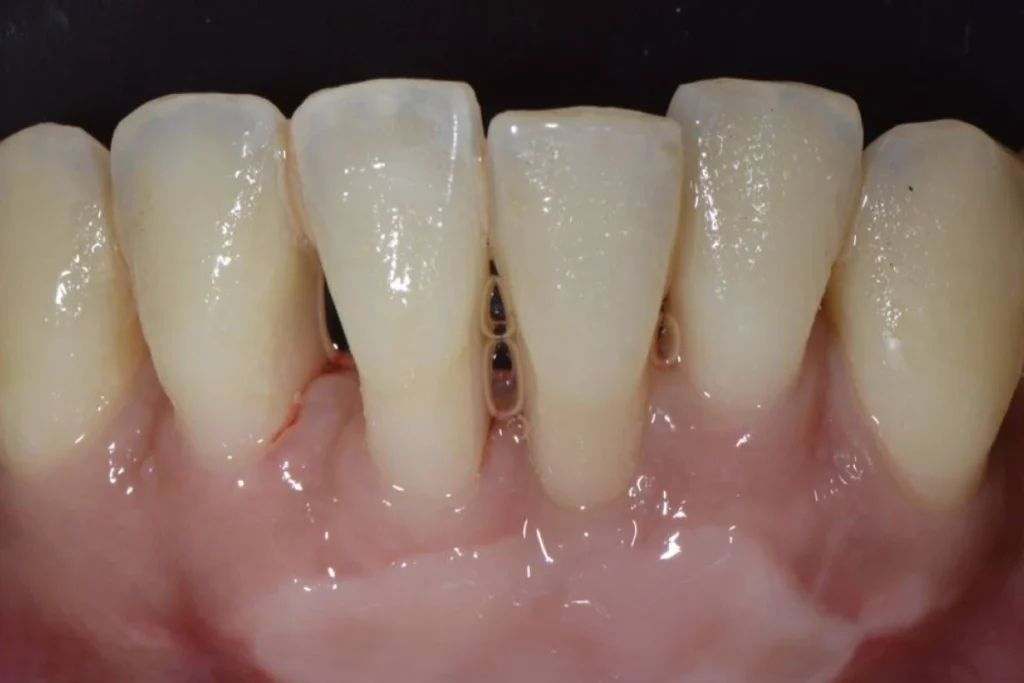

Le fait d’avoir les gencives qui se rétractent laissant apparaitre les racines des dents est appelé Récessions Gingivales.

Très souvent, ces récessions sont d’origine traumatique, dues à un brossage exercé avec une pression excessive et/ou avec une brosse à dents trop dure.

La thérapeutique mise en oeuvre pour rétablir la balance entre la gencive et les dents s’appelle la greffe de recouvrement gingival.

La technique consiste à prélever un greffon dans le palais du patient à l’aide d’un bistouri. Le greffon est ensuite positionné sous la gencive du patient dans la zone où elle fait défaut. L’ensemble est tracté et stabilisé par des sutures pour recouvrir les racines dénudées des dents.

Un pansement est positionné sur le site « donneur » au palais pour faciliter sa cicatrisation. L’intervention est réalisée sous anesthésie locale et se veut complètement indolore. Les suites post-opératoires sont généralement très faciles sur la zone greffée, plus désagréables au niveau du palais où a eu lieu le prélèvement.